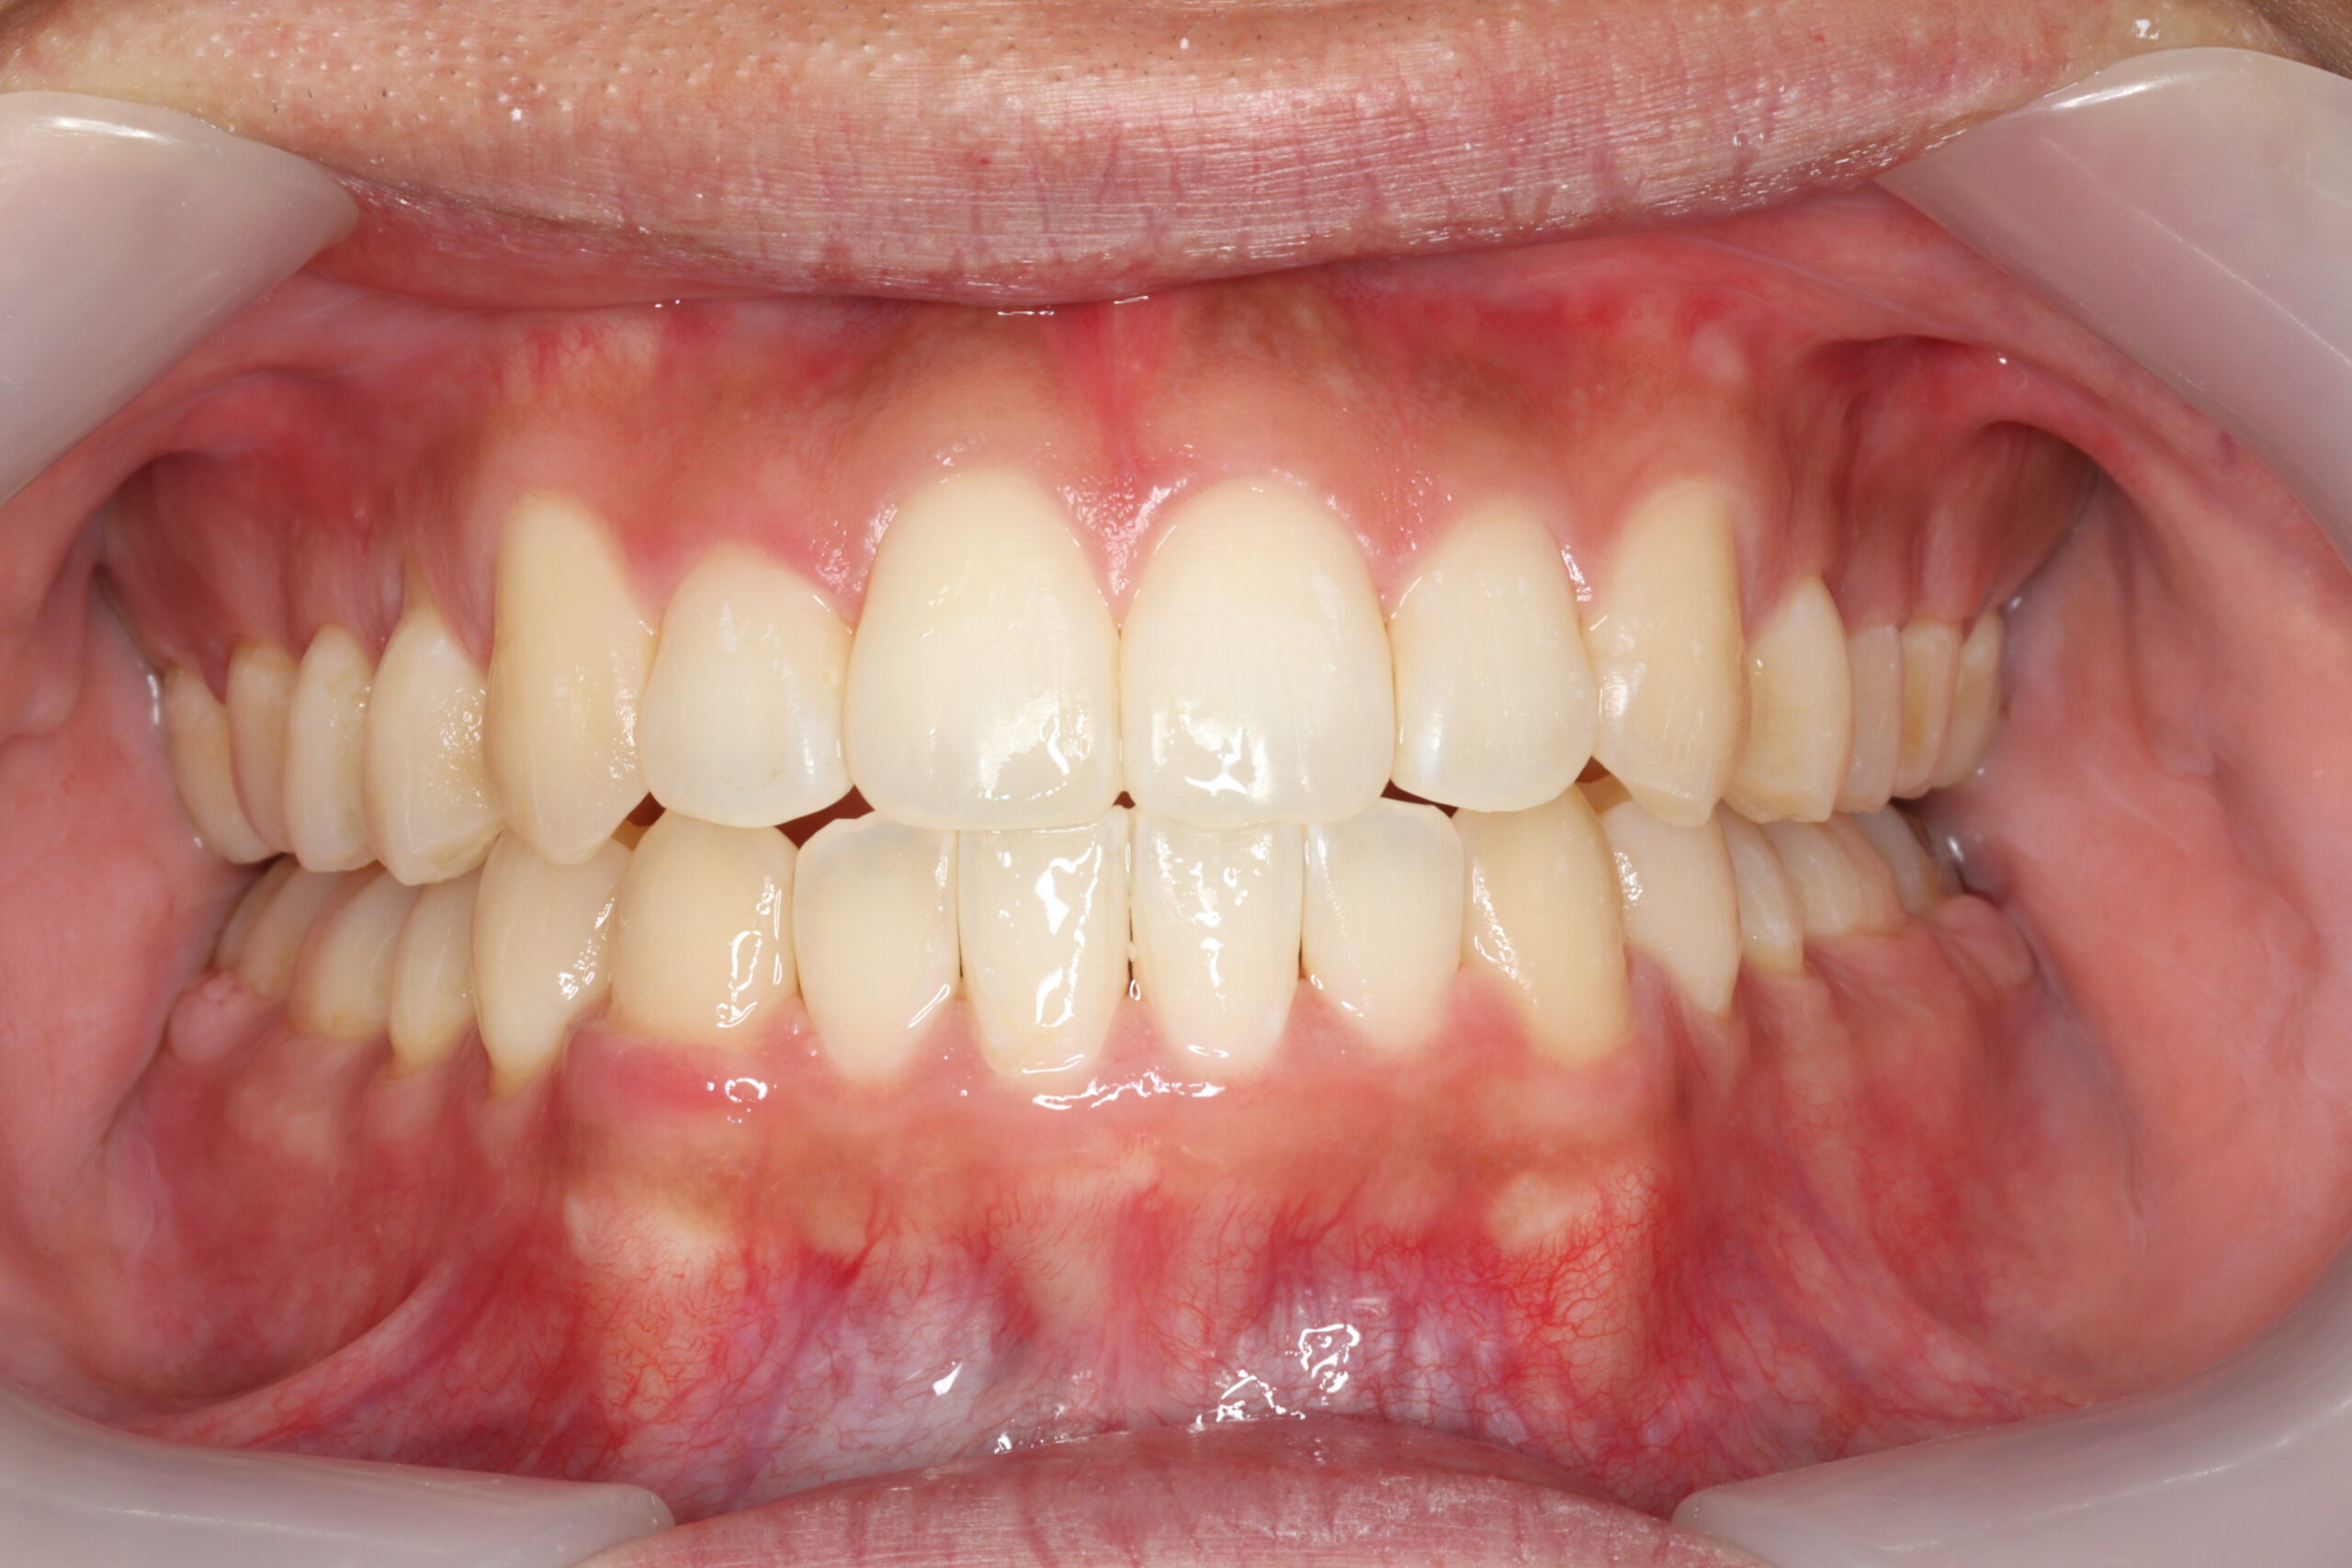

治療後

【診断】開咬、叢生(でこぼこ)、上下顎前歯唇側傾斜、舌突出癖

【治療方法】マルチブラケット装置にて排列を行う。咬合の確立のため顎間ゴムを併用し、舌突出癖の改善のため筋機能療法を行う